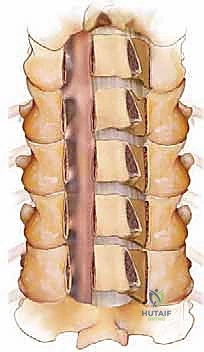

FIG 1 • Anatomy of cervical vertebrae.

FIG 1 • Anatomy of cervical vertebrae.